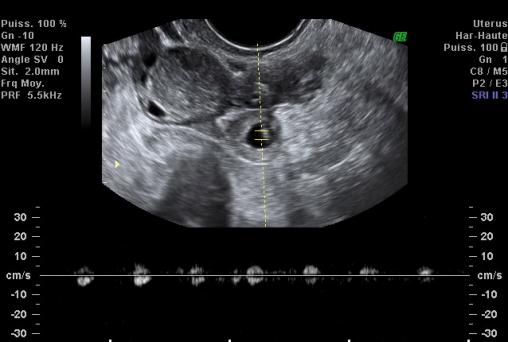

Sac gestationnel extra-utérin

Sac gestationnel extra-utérin avec activité cardiaque.